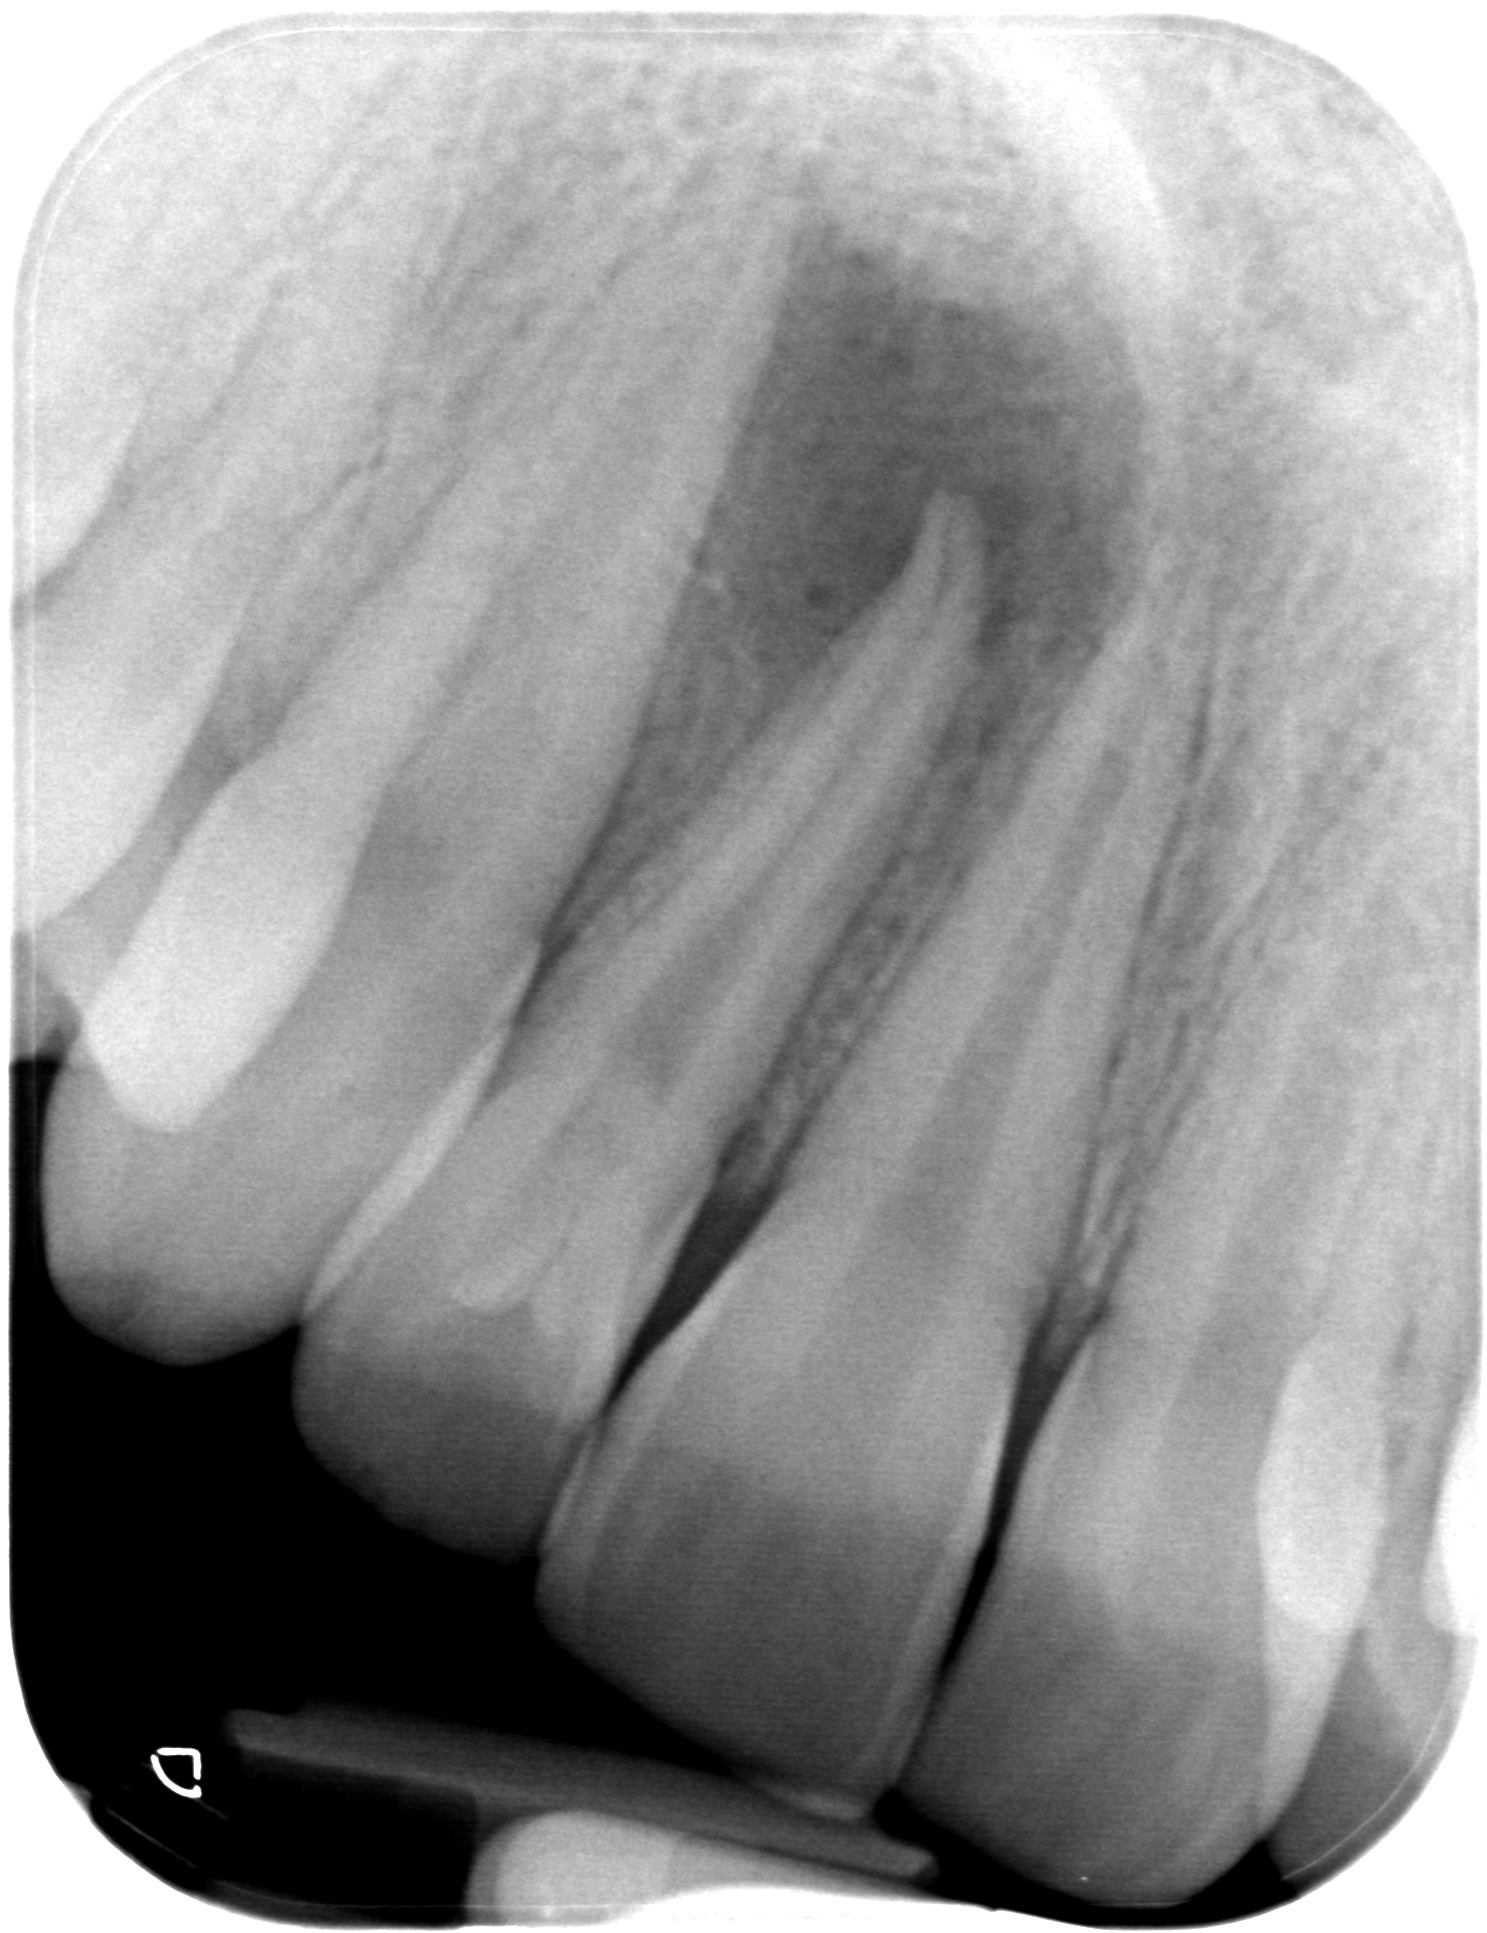

29.04.2019 Patientin LB, geb. am 07.05.2003, Zahn 12, WF-Kontrolle 32 Monate post WF